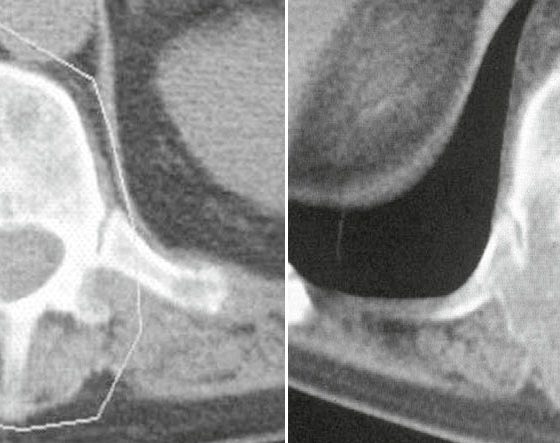

• Radiotherapie bei Knochenmetastasen

Primäre Ziele sind Schmerzreduktion und Funktionserhalt

Bei der Behandlung von Knochenmetastasen ist eine interdisziplinäre Besprechung nötig, um ein optimales multimodales Therapieregime und damit ein bestmögliches Ergebnis für den Patienten zu gewährleisten. Bei unkomplizierten Knochenmetastasen gilt die...…